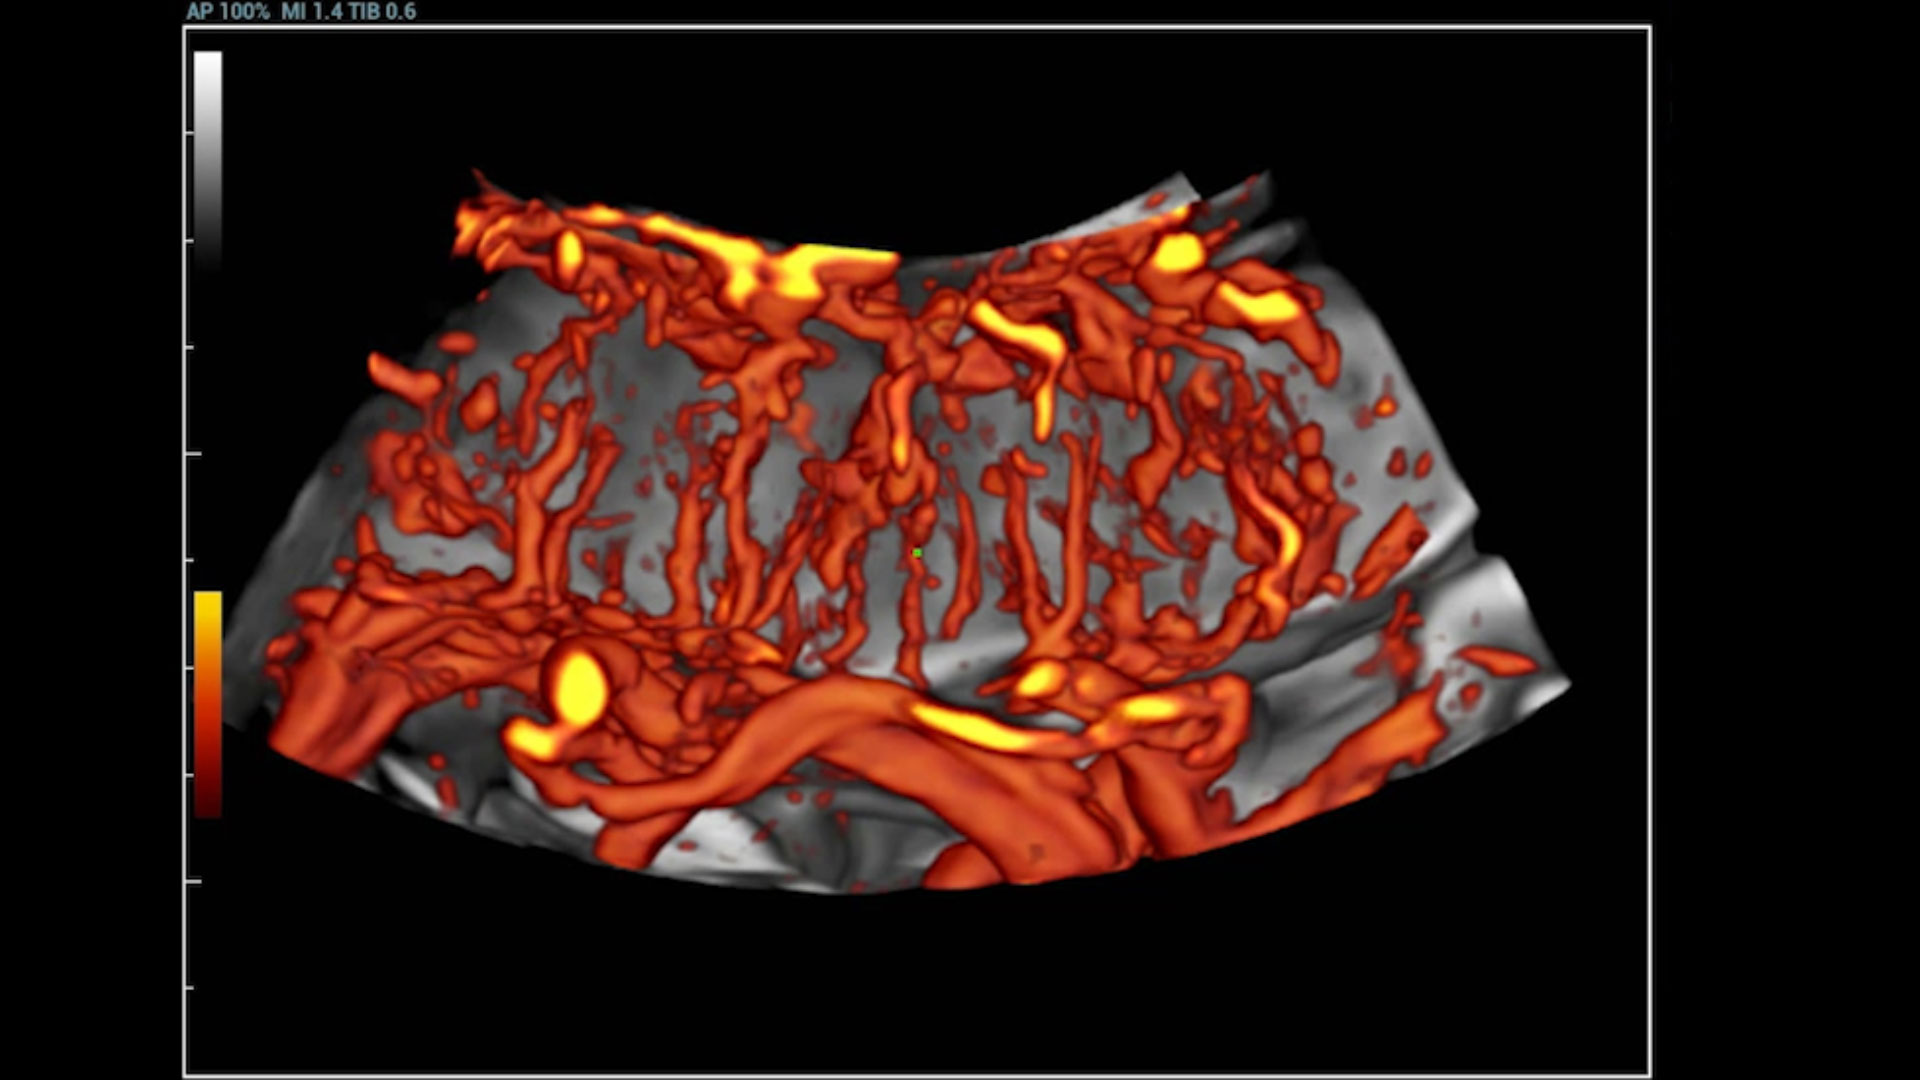

UMA (Ultra-Micro Angiography)

The innovative technology breaks the bottlenecks of traditional Doppler imaging. With ultra-high spatial resolution and flow sensitivity, it allows detecting super-subtle and super-slow flow perfusions, thereby extending the clinical application of qualitative and quantitative ultrasound evaluation in fetal brain, kidney, placenta, endometrium, ovary, etc.

3D UMA - perifollicular blood flow